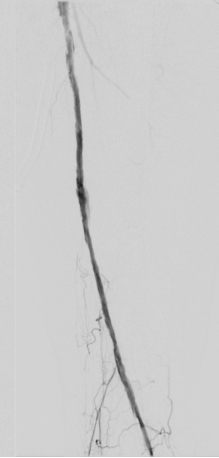

图为:术前造影:腘动脉P3胫前起始部显影

图为:术后造影